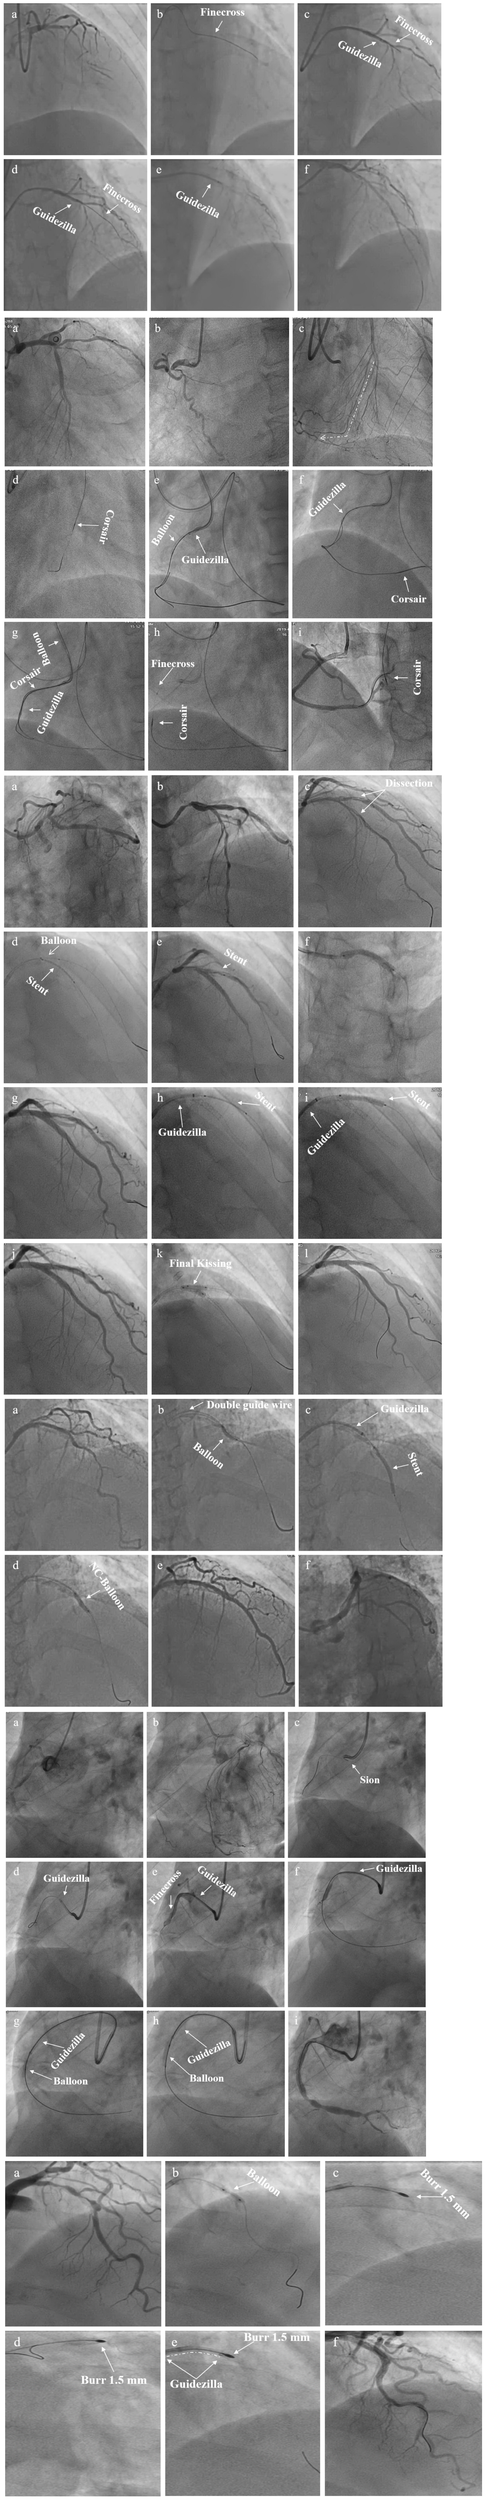

There were 237 target lesions treated, with the majority being type C lesions (95.8%), followed by B2 lesions (4.2%). Among the included cases, there were 104 cases of right coronary artery (RCA; 43.9%), 76 of left ascending artery (LAD; 32.0%), 40 of left circumflex artery (LCX; 16.9%), and 17 of LMCAD (7.2%). The most common indication for GGEC I use was heavy calcification (67%), followed by extreme tortuosity (12.2%), extreme tortuosity and heavy calcification (10.9%), distally located lesion (4.5%), picking up the retrograde wire when using the active greeting technique (AGT; 3.2%), anomalous origin of the vessel (1.8%), and releasing the burr incarceration (0.4%) (Figure 2). The typical examples of using the GGEC I during TRI in different situations are illustrated in Figure 3.

FIGURE 3

Typical examples of TRI using the GGEC I in different situation (Case 1–6). Case 1: an example of percutaneous coronary intervention (PCI) using the Guidezilla™ guide extension catheter I (GGEC I) in left ascending artery chronic total occlusion (LAD CTO) using the antegrade wire approach. A 6F BL3.5 guiding catheter angiography showed the LAD 7-segment CTO (a). Miracle 6.0 was first selected under the support of a Finecross microcatheter, but failed due to insufficient support of the guiding catheter (b). GGEC I was sent along Miracle 6.0 to the LAD 6-segment and then the microcatheter was used to control Miracle 6.0 to smoothly penetrate the proximal fibrous cap of the occlusive disease (c). Miracle 6.0 was then carefully manipulated into the true lumen of the occluded distal blood vessel to the end of the LAD (d). Then, Miracle 6.0 was replaced with Sion via the Finecross microcatheter (e). Finally, the stent was successfully implanted after pre-expansion with balloons of different specifications (f). Case 2: An example of PCI using the GGEC I in right coronary artery (RCA) CTO with retrograde wire approach. TIG angiography showing the LAD 7-segment CTO (a) and RCA 1-segment CTO (b). First, the antegrade wire approach was used to open the LAD, and then the retrograde wire approach was used to open the RCA CTO (c, the white dotted line shows the retrograde pathway used in the operation). Under the support of the Corsair microcatheter, Sion was carefully manipulated through the S1 collateral branch (d) to advance the Corsair microcatheter to the RCA 3-segment along the guidewire, and changed to the UB 3 via the microcatheter; then, UB 3 was directed to the RCA 2-segment through the occluded vessel distal segment. Next, Miracle 6.0 was forwardly manipulated to penetrate the proximal fibrous cap of the occlusive lesion to the RCA 3-segment and the GGEC I was sent along Miracle 6.0 to the RCA1 segment. Then, the Reverse-Controlled Antegrade And Retrograde Subintimal Tracking (R-CART) technique was initiated (e), using Active Greeting Technique (AGT) to reversely manipulate Fielder XT into GGEC I (f). Fielder XT was pushed further forward into 6F SAL 1.0, then anchored with a balloon to push Corsair into 6F SAL 1.0 forcefully (g). The Rendezvous technique failed, and Sion was reverse manipulated into the forward Finecross microcatheter through the Corsair microcatheter, and the Finecross microcatheter was pushed forward to the posterior branches of left ventricular (PL) along Sion while withdrawing the Corsair microcatheter backward (h). Stents were implanted after dilating the occluded blood vessel with predilated balloons of different sizes along the guidewire after the Finecross microcatheter was removed (i). Case 3: An example of PCI using GGEC I in both LM and LAD bifurcation lesions. 6F JL3.5 angiography showed approximately 80% stenosis of the LM end, 50-80% stenosis of the LAD 6-7 segment, and subtotal occlusion in the proximal segment of D1 (a,b). The two Runthroughs were carefully manipulated to enter the ends of the LAD and D1, respectively, and narrow lesions were expanded with a balloon, resulting in residual stenosis of approximately 50% in the LM end, and severe dissection of LAD7 and proximal D1 with thrombolysis in myocardial infarction (TIMI) flow grade 3 as seen by angiography (c). The Crossover strategy was used to treat LM bifurcation lesions, and the inverse mini-crush technology was used to treat LAD and D1 bifurcation lesions (d). However, after repeated attempts, it was difficult for the stent to enter D1 and completely cover the lesion (e), so a stent was immediately implanted in LM-LAD (f). Angiography showed that the stent was fully expanded, with a blood flow of TIMI level 3 (g). Next, a GGEC I was sent along the guidewire to the opening of D1, and a stent successfully sent to D1 via the GGEC I and completely covered the lesion (h). After withdrawing the GGEC I to the LAD opening, the stent was successfully released in the D1 (i). Angiography showed that the stent was fully expanded and the blood flow was TIMI level 3 (j). Finally, by rewiring the Runthrough into the LAD and completing the Final Kissing step (k), the operation was a success (l). Case 4: An example of PCI using the GGEC I in LAD with extreme tortuosity and severely calcified lesions. 6F EBU 3.75 angiography showed extreme tortuosity and heavy calcification in LAD 6–8 segments with approximately 80% stenosis (a). Two Runthroughs were manipulated to reach the end of the LAD through the stenosis, and Sprinter 2.0 × 15 mm and NC Sprinter 2.5 × 15 mm were pushed into place in turn with difficulty, under the support of a double guidewire, which was used to expand the stenosis under high pressure (20–24 atm) (b). Then, three stents were implanted via the GGEC I from distal to proximal LAD 6–8 (c). Finally, NC-balloons of different figures were selected to expand the stents under high pressure (20–24 atm) (d), and angiography showed that the stents were fully expanded with a blood flow of TIMI 3 (e,f). Case 5: An example of PCI using the GGEC I in CTO of the RCA with abnormal opening. Angiography showed that the ascending aorta was significantly widened, the end of RCA 2 segment showed localized occlusion, and the bridging collaterals supplied blood to make the distal vessels partially visible (a). The LAD provided the collaterals, and the RCA was retrogradely perfused to the end of segment 3 (b). It was difficult to keep the 6F AL 1.0 guiding catheter in place, and Sion was patiently manipulated to “float” into the RCA (c). Then, the GGEC I was slowly pushed along Sion into the RCA (d). Sion was exchanged with Conquest pro 8–20 via the Finecross and manipulated carefully through the occluded segment (e) and into PL (f) under multi-position fluoroscopy. Under the support of the GGEC I, pre-expansion was performed using balloons of different specifications (g,h). Finally, the stent was successfully implanted in the occlusive segment (i). Case 6: An example of PCI using the GGEC I to release the burr incarceration. 6F EBU 3.75 angiography showed heavy calcification in LAD 6-8 segments with about 90% stenosis (a). Runthrough was carefully manipulated to reach the end of the LAD through the narrow lesions, and NC Trek 2.0 × 12 mm was selected for high-pressure dilatation (20–24 atm). However, the balloon was still not fully expanded, and the body had obvious indentation (b). Rotational atherectomy was started and a 1.5-mm burr was passed through the stenosis successfully, but it was incarcerated during the third polishing process (c). The first attempt to insert a second guidewire and dilate the stenosis near the burr with balloon was unsuccessful (d). The rotational catheter was immediately cut off, and the GGEC I was sent into the guiding catheter. It reached the LAD 6 segment along its inner core. After wrapping it tightly with the non-invasive head end of the GGEC I (dotted white line), the burr was successfully removed from the body together with the GGEC I (e). Finally, stents were successfully implanted after NC-balloon dilation (f).